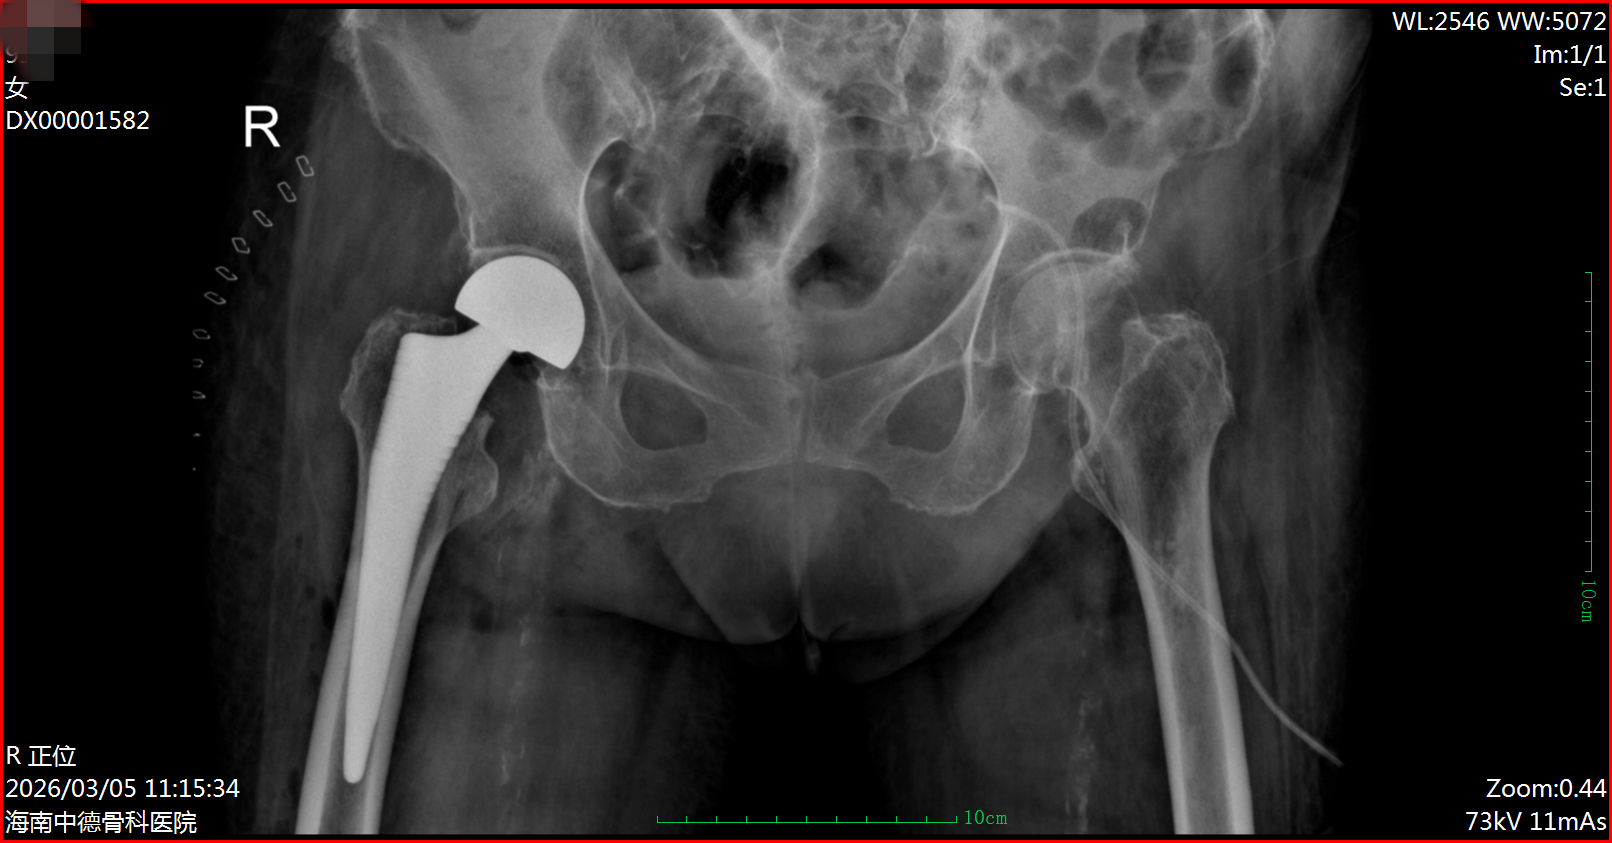

术后DR片

顺利转归 彰显综合救治实力

经过多学科无缝衔接的精心治疗与护理,患者生命体征日趋平稳,于3月7日成功转回普通病房,神志清晰,状态良好。